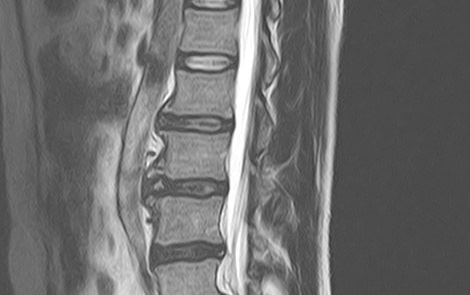

1.5テスラMRI装置Vantage Elan(キャノンメディカルシステムズ製)を導入しておりレントゲン検査では評価しづらい骨の内部や軟部領域の精査が可能で、脊椎・四肢など整形外科領域の幅広い部位の検査を行っています。撮影部位にもよりますが検査には約20~40分ほど時間がかかります。低侵襲で安全な検査ですが強い磁気を使うので金属類は外して検査を行います。通常予約待ちの多いMRI検査ですが当院では医師の指示のもと初診時の当日検査も可能でスムーズかつ的確な診断、検査待ちの解消にも努めています。